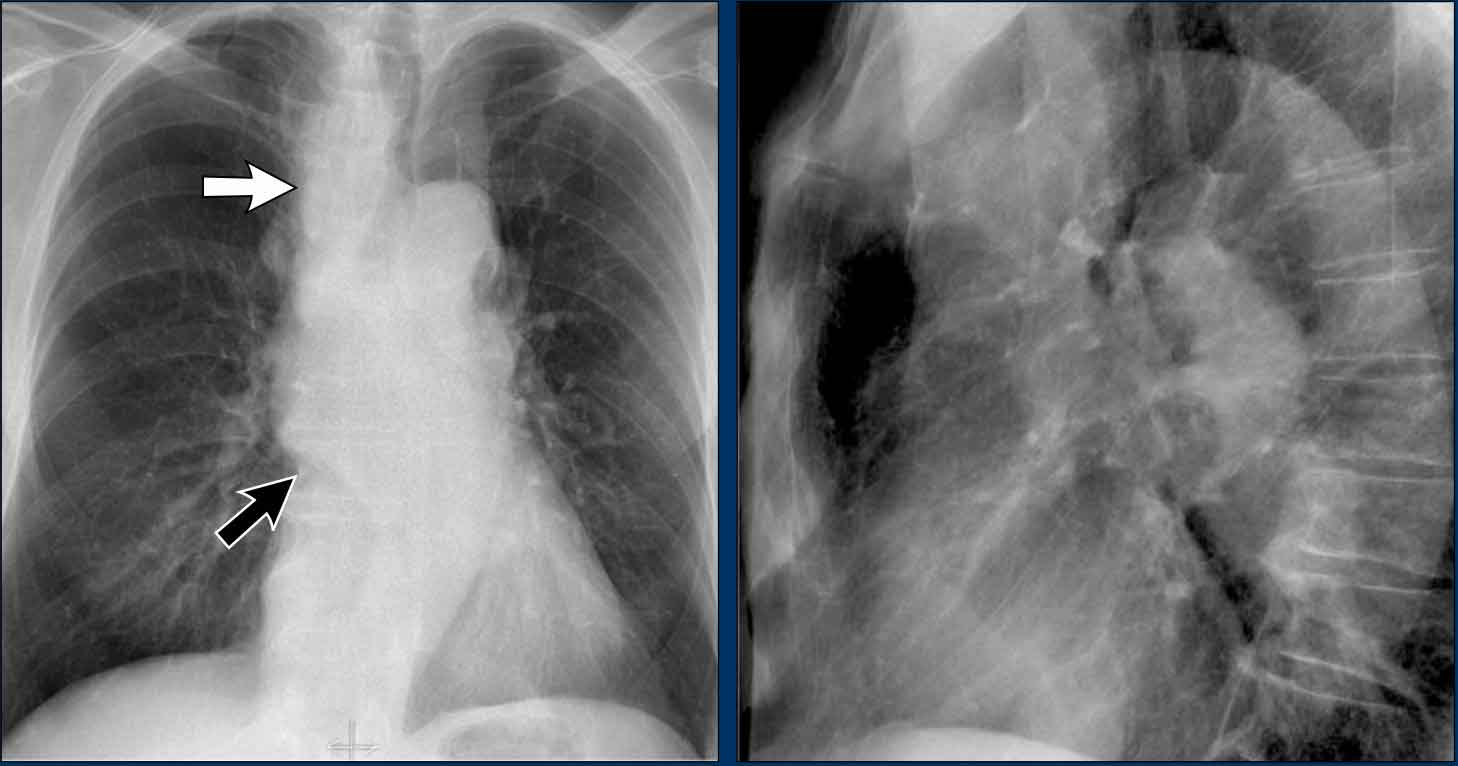

Displacement of the Azygoesophageal Line (2) – Subcarinal Lymphadenopathy

A common cause of displacement of the azygoesophageal line is subcarinal lymphadenopathy (station 7).

On the chest X-ray, note superior displacement of the azygoesophageal line just below the carina, consistent with enlarged subcarinal lymph nodes (black arrow).

Additional right paratracheal lymphadenopathy is seen, displacing the right paratracheal stripe (white arrow) and deviating the trachea to the left.

Continue with PET-CT...

PET Imaging

• PET-CT demonstrates extensive hypermetabolic lymphadenopathy in the mediastinum and neck, which is more conspicuous than on chest radiography.

• Cervical lymph nodes are involved—an important finding as they are accessible for biopsy.

Continue with images of CT and ultrasound...

CT Imaging

• Contrast-enhanced CT shows bulky subcarinal lymphadenopathy displacing the azygoesophageal recess and compressing the left atrium.

• Biopsy of a cervical node confirmed small cell lung carcinoma.